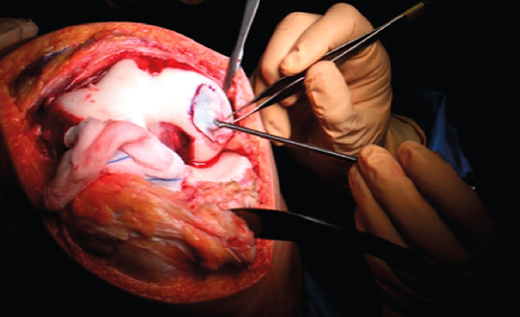

- A paramedial joint incision is made, with luxation of the knee and access to the lesion (Figure 6).

- The damaged cartilage is cleaned using curettes, with debridement of the defect, and the lesion is left with healthy and exposed subchondral bone (Figure 7).

Figure 6. Internal paramedial incision of the knee.

Figure 7. Debridement of the damaged cartilage.